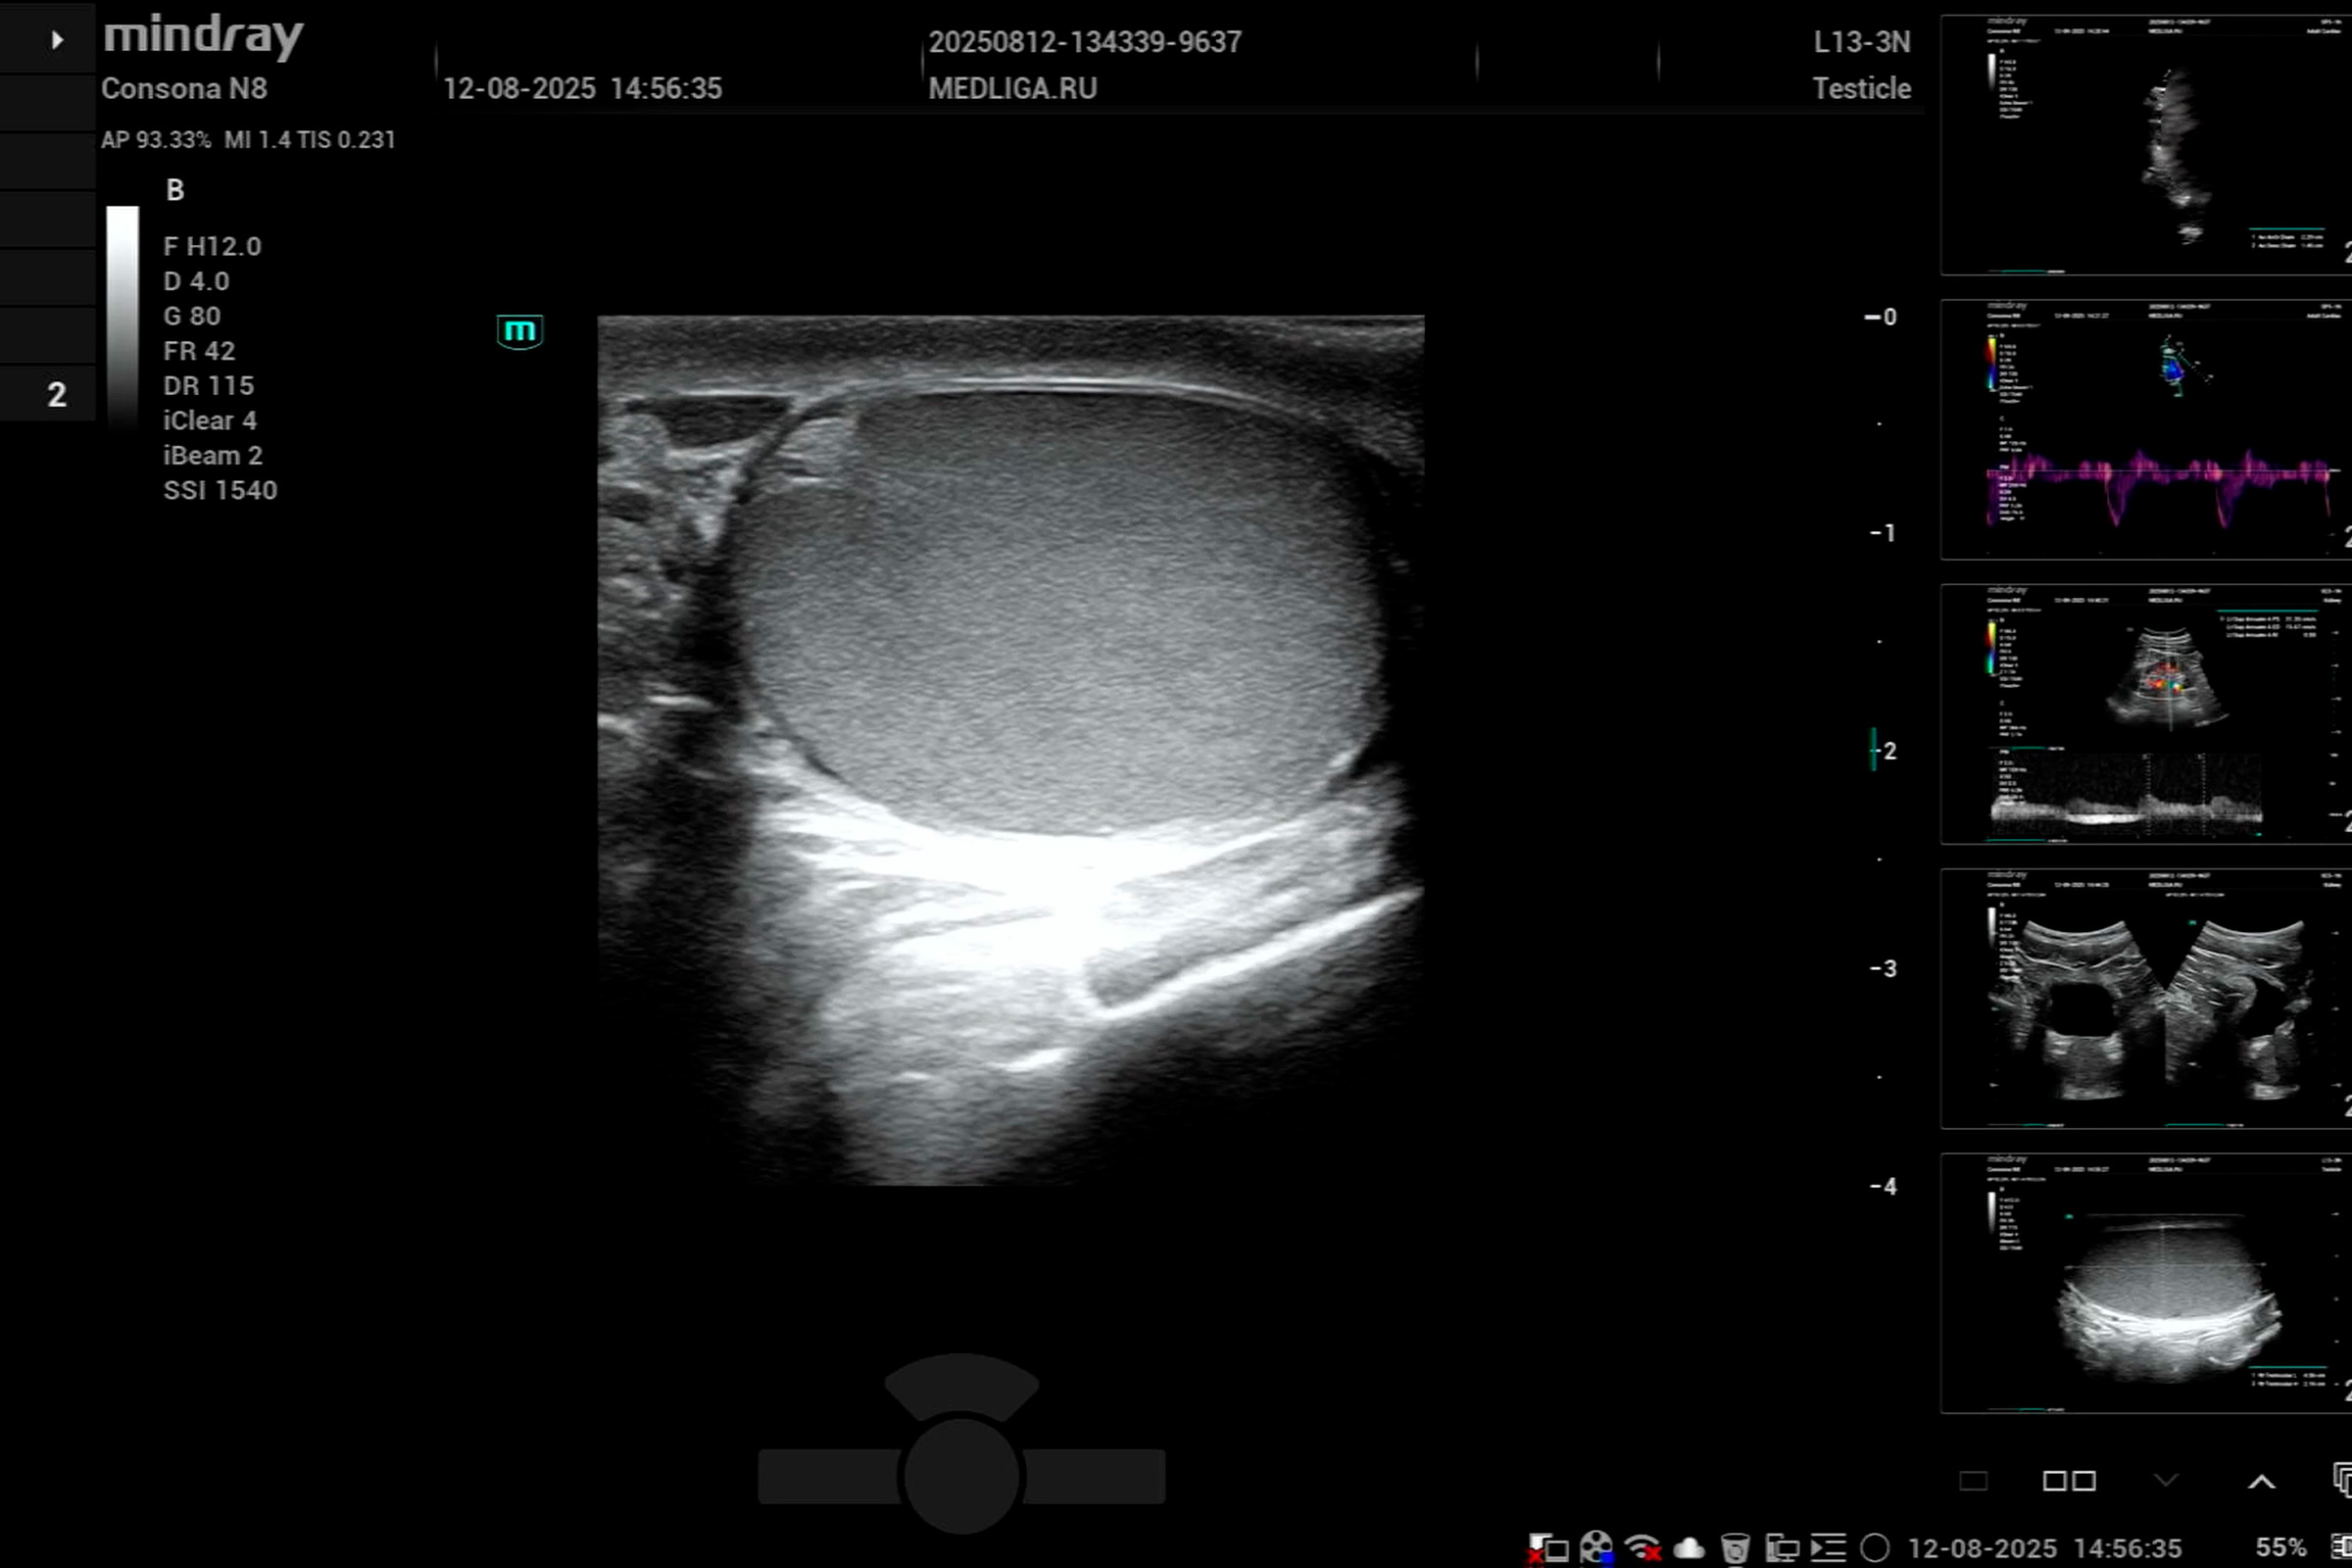

Медицинское оборудование для ультразвуковой диагностики